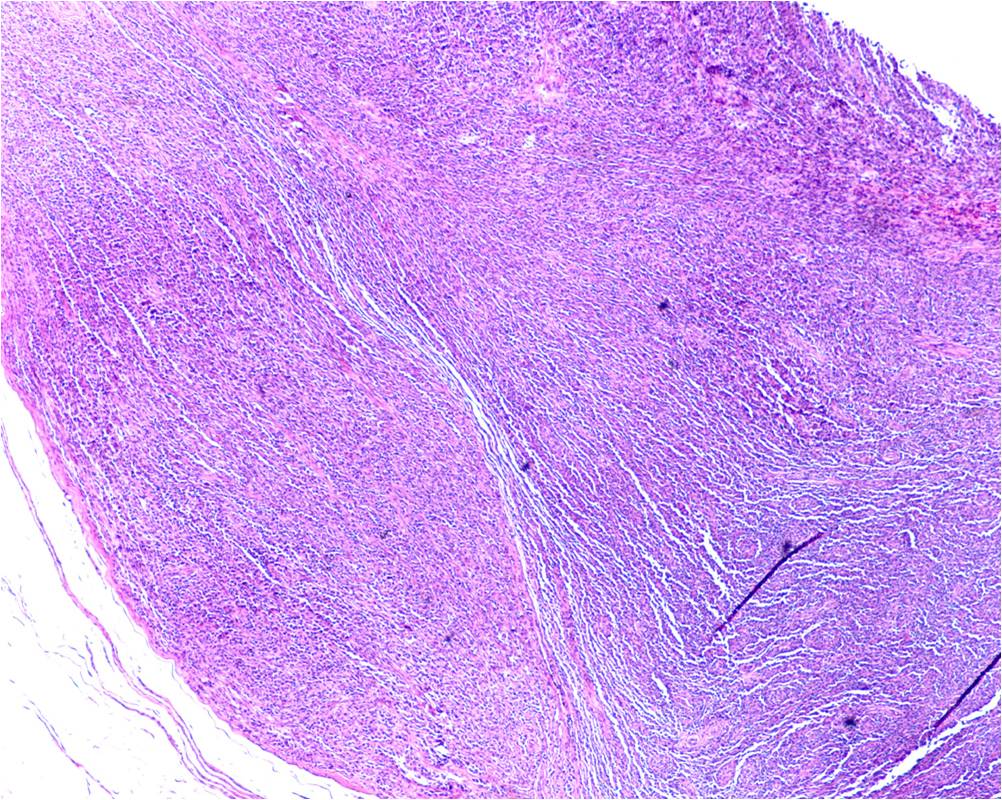

Fig. 5

Fig. 6

Fig. 5-7: Microscopic Pathology. Low (Fig. 5), Intermediate (Fig. 6) and High (Fig. 7) power view shows polygonal and elongated shaped cells with acidophilic cytoplasm and prominent nucleoli, with fascicular growth pattern, delineated by fibrous septa. There is a considerable amount of clear cytoplasm around the atypical epithelioid nuclei. There is minimal pleomorphism, low mitotic rate and no evidence of necrosis.